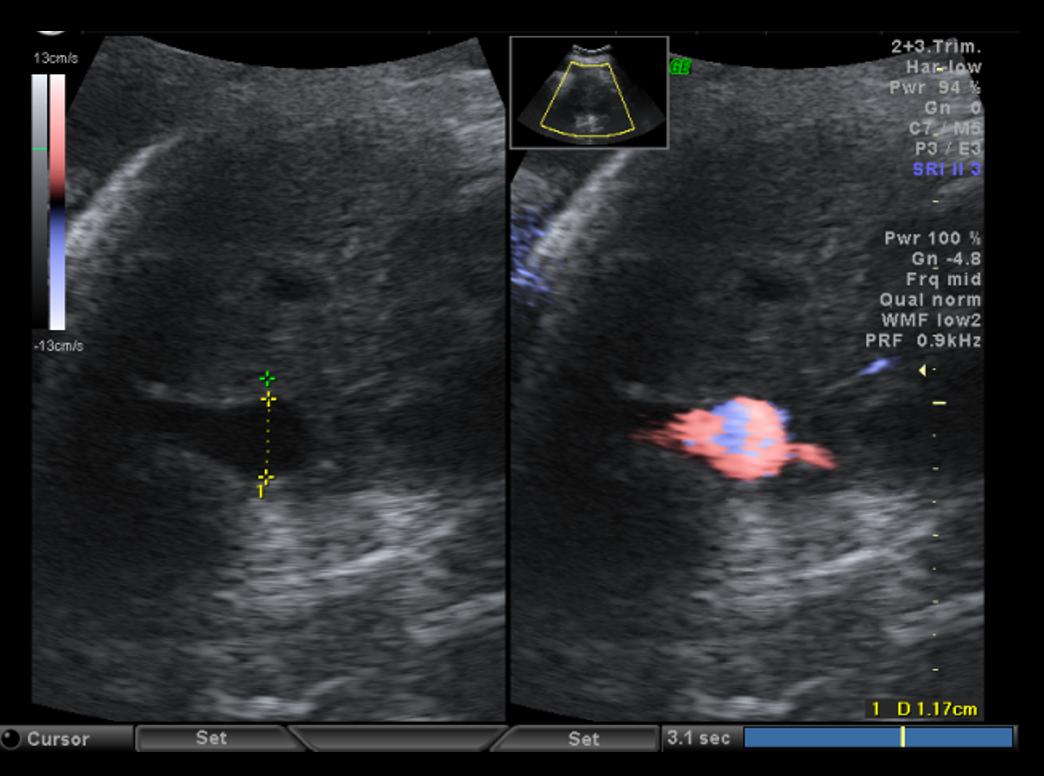

Diagnostic criteria for UVV and the WFUP protocol for subsequent evaluation and surveillance is described in (Table 1) and was followed for all maternal-fetal pairs. UVV characteristics documented during each ultrasound included: size, directionality of blood flow (unidirectional or bidirectional), presence of turbulence, and presence of a filling defect; see (Figures 1a-1c).

Figure 1a. Unidirectional or nonturbulent flow without filling defect.

Figure 1b. Bidirectional or Turbulent flow without filling defect.

Figure 1c. Bidirectional flow with suspected filling defect.

Filling defects were recorded when sonolucent absence of color flow was demonstrated with color Doppler within the UVV. Filling defects were interrogated in transverse and sagittal abdominal views along with color Doppler sweeps to confirm the filling defect and overcome the artifact loss of signal with flow perpendicular to insonation. The presence of UVV and its characteristics was confirmed on repeat ultrasound within 7 days while having monitoring in the interim for fetal well-being. All recorded fetal sonographic measures were uniformly collected by WFUP’s American Institute of Ultrasound in Medicine (AIUM) accredited ultrasound unit by a Registered Diagnostic Medical Sonographer. Voluson E10 General Electric ultrasound machines, with abdominal probe 4-8 and 4 mHz frequency, were used. All WFUP patients are offered genetic counseling and genetic screening as appropriate, including this study’s participants.